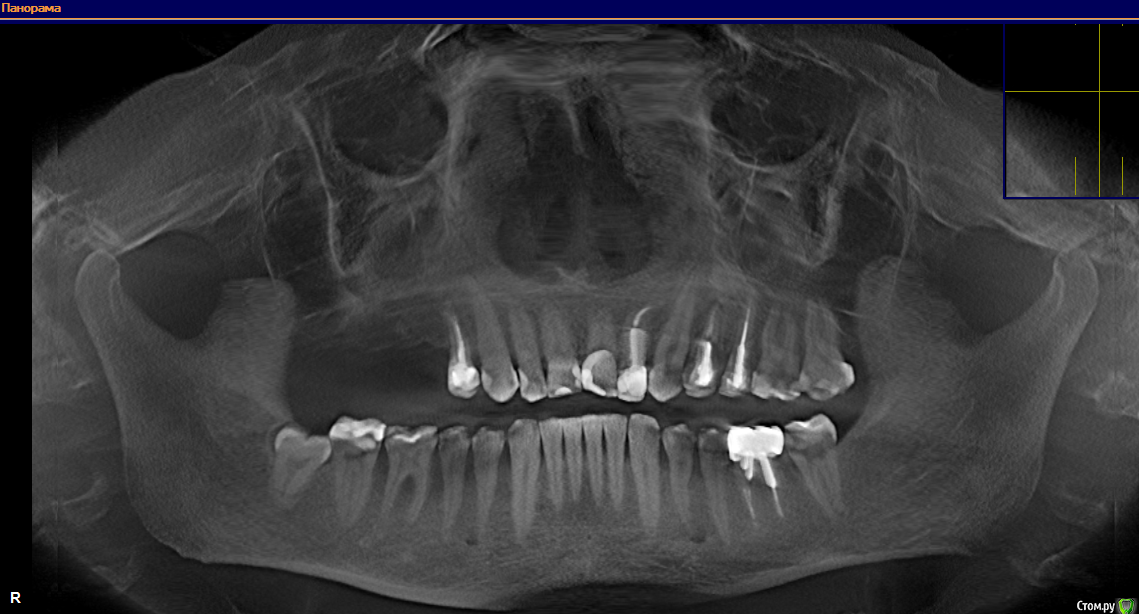

Alcort Опубликовано 6 декабря, 2018 Поделиться Опубликовано 6 декабря, 2018 (изменено) Добрый вечер. Врач уверяет меня в том что необходимо удалить зуб №12 но у меня там уже коронка стоит свежая совсем. Задал вопрос другому ортопеду, ответ еще суровее, под вопросом так же зубы №14 и 19 но они меня не беспокоят как и двенадцатый. Предлагают вкрутить имплантат за место зуба №12 Как же быть? Есть 3D томография обеих челюстей. Здесь iso образ диска который можно замонтировать даймонт тулсом например, всего 300 мегабайт.https://yadi.sk/d/uE1Lyitu0a-QkA Изменено 6 декабря, 2018 пользователем Alcort Ссылка на комментарий

Alcort Опубликовано 6 декабря, 2018 Автор Поделиться Опубликовано 6 декабря, 2018 (изменено) Извиняюсь если ошибся, удалить предлагают четверку с верху с лева (премоляр рядом с клыком, он под коронкой Empress) сказали что там кариес корня судя по 3D снимку, а под вопросом левые шестерки верхняя и нижняя. Но не один из трех зубов меня не беспокоит. Изменено 6 декабря, 2018 пользователем Alcort Ссылка на комментарий